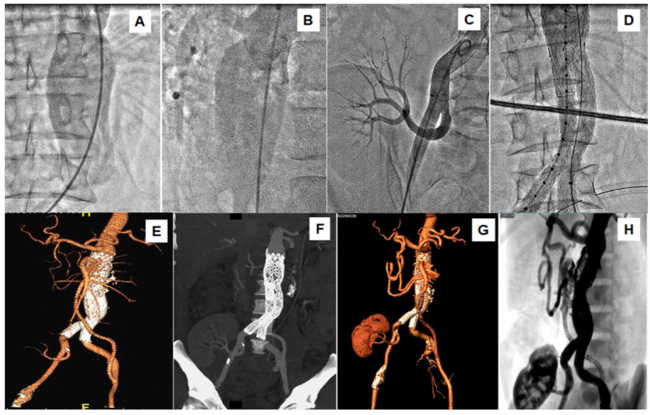

A 45-year-old man presented with pain in the abdomen and pulsatile abdominal swelling of 3-month duration. He had kidney transplantation for chronic kidney disease 2 years prior. Computed tomography (CT) angiography revealed a 10.0-cm x 6.5-cm juxtarenal, fusiform abdominal aortic aneurysm (AAA), extending from the origin of the superior mesenteric artery (SMA) to the aortic bifurcation. A hybrid aortic intervention was planned. A polytetrafluoroethylene (PTFE) bypass graft was anastomosed from the left external iliac artery to the SMA. A contrast aortogram confirmed the CT angiography finding (ie, AAA extending from the origin of SMA to aortic bifurcation) (Figure 1A and Figure 1B), normal transplanted renal artery (Figure 1C), and patent bypass graft to SMA. A bifurcation stent graft (Gore Excluder AAA endoprosthesis) was implanted. The main body 31-mm x 14.5-mm x 170-mm size was implanted below the origin of the celiac trunk, extending up to the left common iliac artery. The side branch 14.5-mm x 120-mm size was implanted from the right side, covering the right common iliac artery (Figure 1D and Video Series). A repeat CT angiogram at 1-year follow-up showed patent bifurcation stent graft and SMA bypass graft, and normal transplanted renal artery (Figure 1E and Figure 1F). A recent CT angiography at 11 years of asymptomatic follow-up revealed a patent stent graft without any endoleak and patent transplanted renal artery (Figure 1G and Figure 1H). The PTFE bypass graft to SMA was occluded. There were adequate collaterals from the celiac trunk (gastroduodenal and pancreaticoduodenal arcade) to the proximally occluded SMA (Figure 1G and Figure 1H).

The index case demonstrated the favorable long-term outcome of endovascular aortic repair for juxtarenal AAA in a post-renal transplant patient.